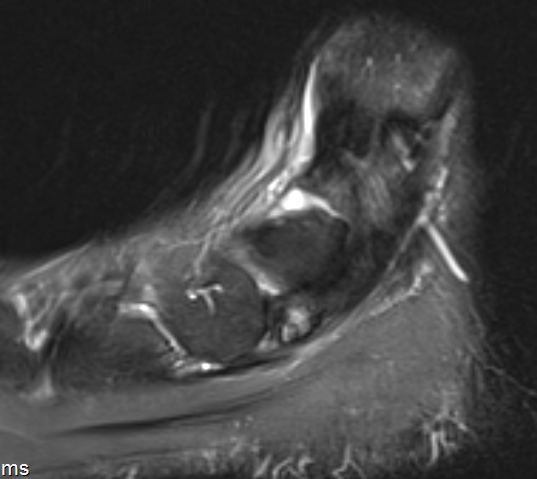

Bone Scan

MRI

Show edema about a symptomatic accessory navicular